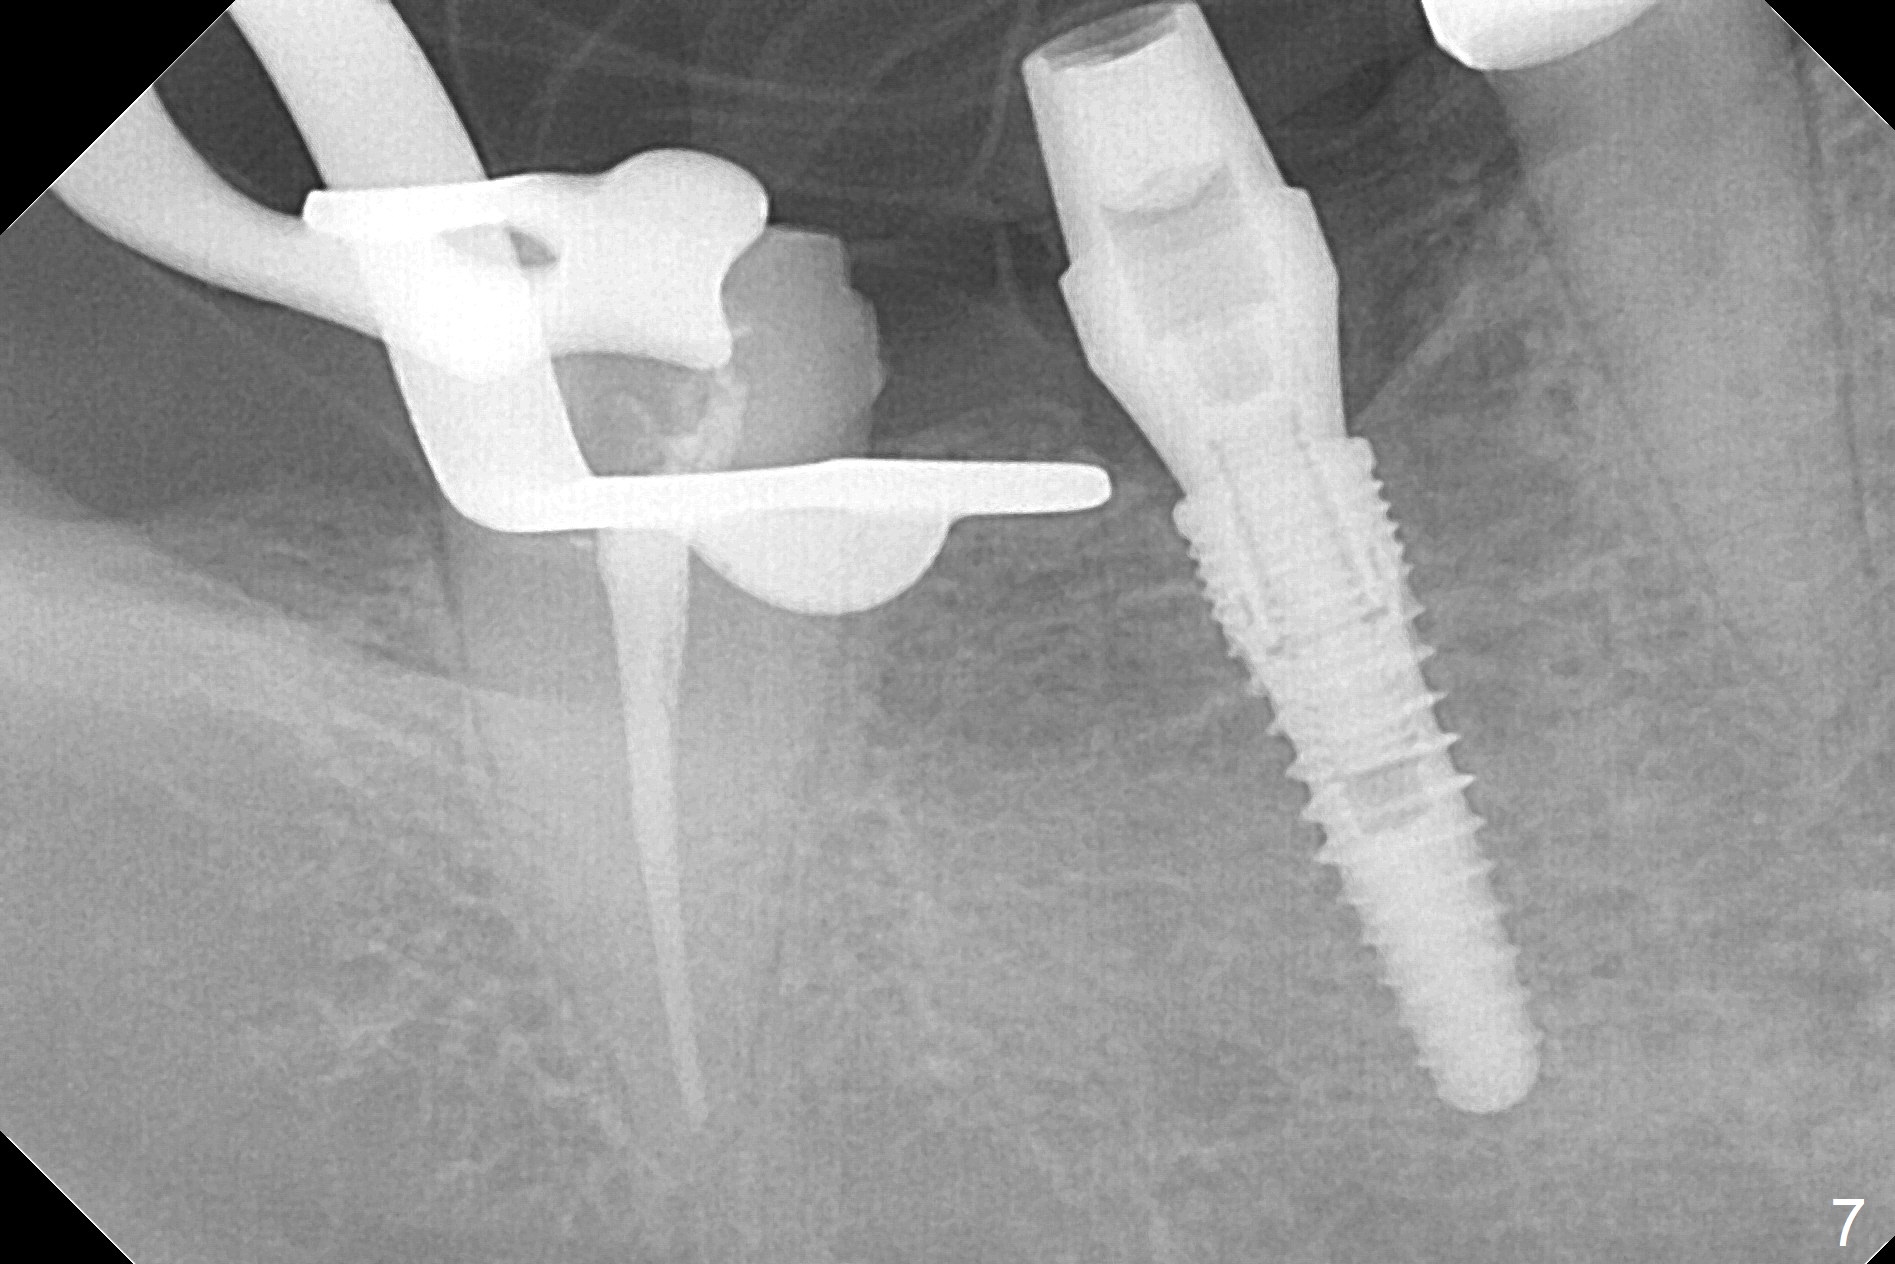

The apparently narrow ridge at #30 before bridge sectioning (Fig.1) is confirmed with incision (Fig.2). Following ridge reduction, osteotomy is initiated with 2 mm pilot drill (Fig.3). When a 3.8x12 mm SM narrow implant is placed with 40 Ncm, there is 1-2 mm cortical bone buccolingually (Fig.4,5). The thick cortices do not seem to be easy to be bent, i.e., expanded. RCT is finished at #31 one month post implant placement (Fig.6,7), the flattened ridge appears to have started to undergo remodeling. Ridge reduction makes it possible for the implant to remain subcrestal postop (Fig.4). The bone surrounding the implant may reduce the likelihood of implant fracture. The crowns at #30 and 31will be fabricated together with light occlusion at #30. In fact the splinted provisional dislodges. There appears dense bone formation 3 months postop (Fig.8 *). The drawback of using a SM narrow implant is that a narrow abutment has to be used (4.8x4(4.5) mm). The implant crown is dislodged immediately after the patient finishes lunch. Following recementation, the occlusion is reduced. In fact, UF or IBS has no such drawback: the implant could be small, but the abutment could be large. One year post cementation, the crown at #31 needs recementation (Fig.9); the bone density next to the coronal implant increases (*).